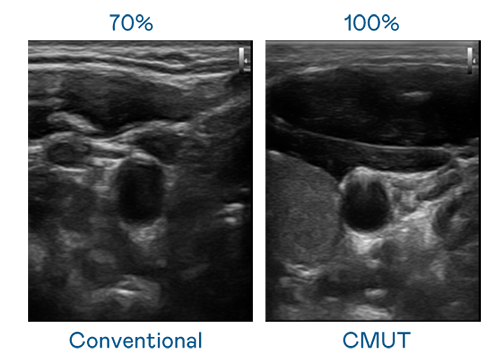

CMUT 技术是一种用电容式微机电元件来产生超音波讯号的技术。与传统 PZT 压电式技术相比,CMUT 频宽增加 30%,更宽频的超音波讯号让影像解析度大幅提升,是实现高影像品质医疗超音波扫描、促进精准医疗发展的关键技术。

超音波影像的解析度高低,首先取决于探头能发出的讯号频宽。HJC黄金城 CMUT 可提供高清晰的超音波讯号,提供高频宽、高灵敏度、影像纹理细节更高的超音波影像,协助医护人员缩短影像判读时间及利用精准的医疗影像进行诊断。